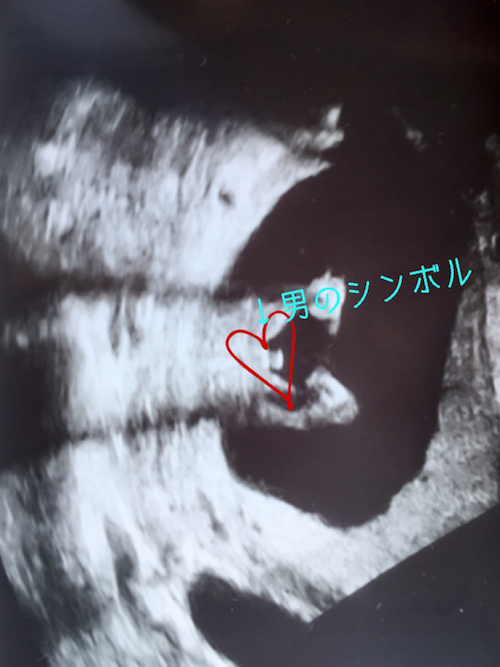

15週0日(15w0d・男の子)|タイガーアヤ さん(33歳)

エコー写真撮影時のエピソード:

初めての性別判断の日でした。

しっかりと男の子のシンボルマークが見えてすごく嬉しかったです。その時はすごく赤ちゃんも動いていて、手を振っているような仕草で先生と大笑いしました。

どちらでもいいと言っていたパパもエコー写真を見て男の子と知り、すごく嬉しそうな表情をしていました!